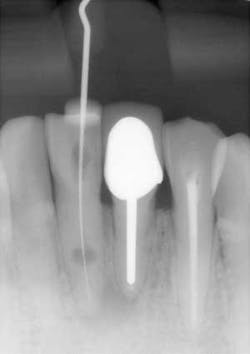

- This is another case of what could easily be misdiagnosed as internal resorption on tooth #No. 24. If you look closely in Figure 7, the outline of the canal can be seen.

- In Figure 8, the lesion is advanced significantly (one-and-a-half years had gone by) the irregular borders and moth-eaten appearance is easily observed.

- Definitive diagnosis: external resorption.